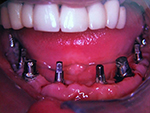

Kugelkopf-Implantation: